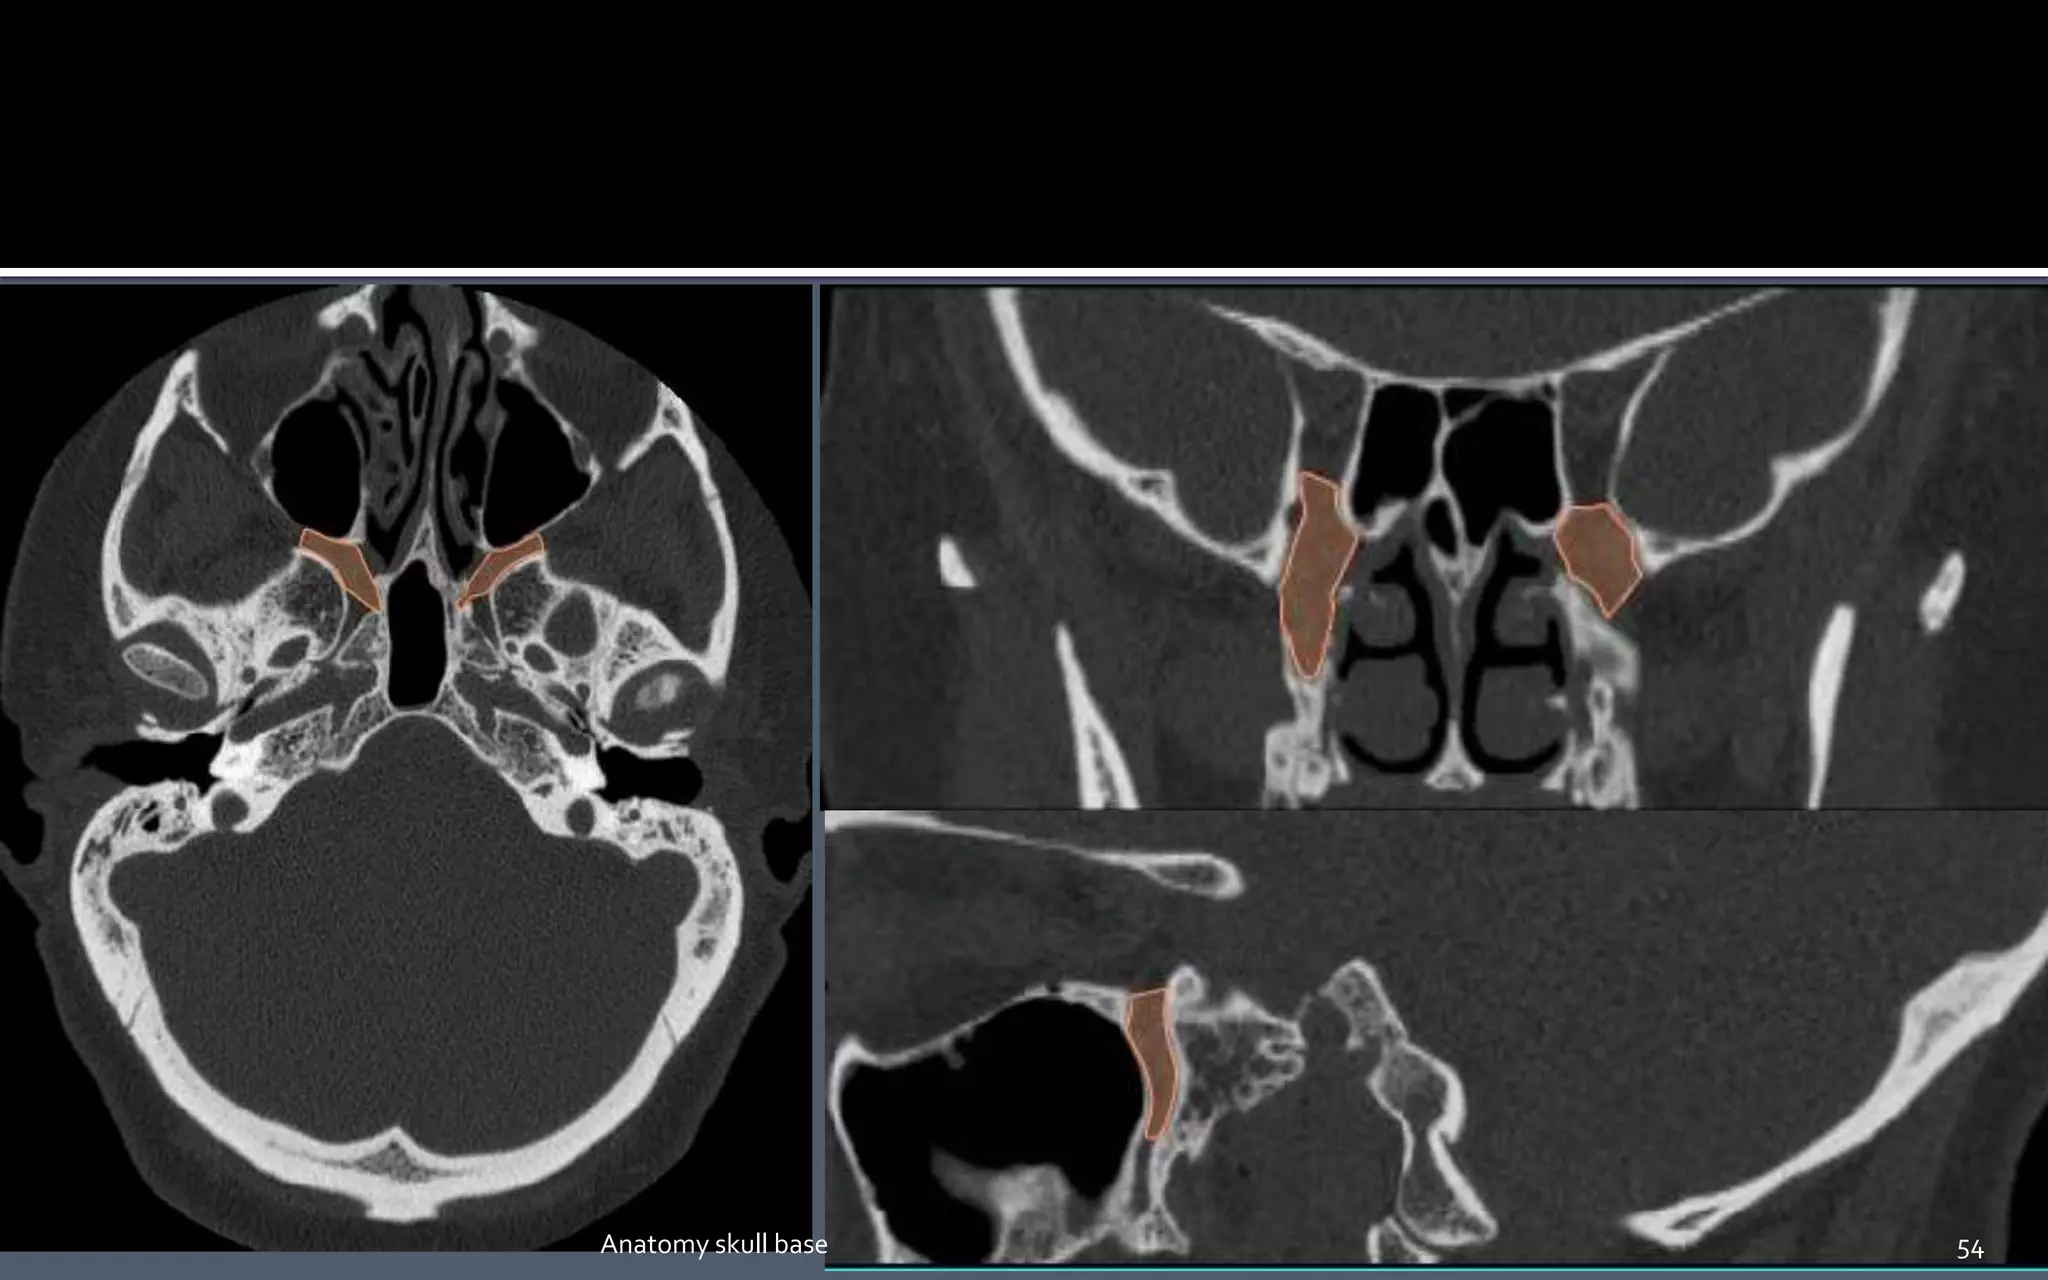

 A fat filled space between the pterygoid

plates and the posterior wall of maxillary

sinus.

 Shaped like an inverted pyramid.

Borders :-

The walls of the PPF are as follows:

Medial - perpendicular plate palatine bone.

Lateral - narrowing to pterygomaxillary fissure

Anterior - posterior wall of maxillary sinus

posterior - Medial and lateral pterygoid plates;

inferior aspect of lesser wing of sphenoid bone

52Anatomy skull base

 The PPF is an important pathway for the spread of neoplastic and infectious

processes:

Medially - communicates with the nasal cavity via the sphenopalatine foramen.

Laterally - communicates with the masticator space (or infratemporal fossa) via

the pterygomaxillary fissure.

Anteriorly - communicates with the orbit via the inferior orbital fissure.

Posteriorly and superiorly - communicates with the Meckel cave and cavernous sinus (of

the middle cranial fossa) via the foramen rotundum.

Posteriorly and inferiorly - communicates with the middle cranial fossa via the vidian

canal, which transmits the Vidian nerve.

Inferiorly - communicates with the palate via the greater and lesser palatine canals 53

 A fatfilled space between the pterygoid plates and the posterior wall of maxillary sinus.  Shaped like an inverted pyramid. Borders :- The walls of the PPF are as follows: Medial - perpendicular plate palatine bone. Lateral - narrowing to pterygomaxillary fissure Anterior - posterior wall of maxillary sinus posterior - Medial and lateral pterygoid plates; inferior aspect of lesser wing of sphenoid bone 52Anatomy skull base

 The PPFis an important pathway for the spread of neoplastic and infectious processes: Medially - communicates with the nasal cavity via the sphenopalatine foramen. Laterally - communicates with the masticator space (or infratemporal fossa) via the pterygomaxillary fissure. Anteriorly - communicates with the orbit via the inferior orbital fissure. Posteriorly and superiorly - communicates with the Meckel cave and cavernous sinus (of the middle cranial fossa) via the foramen rotundum. Posteriorly and inferiorly - communicates with the middle cranial fossa via the vidian canal, which transmits the Vidian nerve. Inferiorly - communicates with the palate via the greater and lesser palatine canals 53